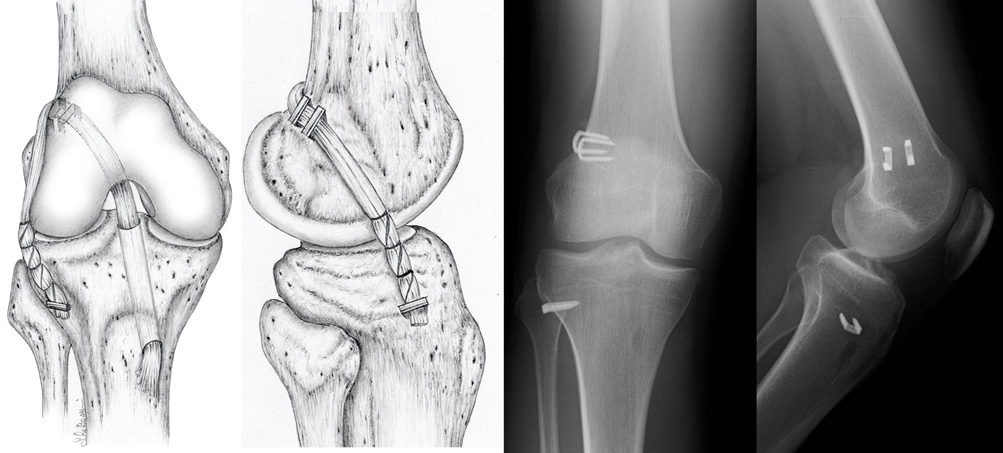

Nella maggior parte dei casi si procede a un prelievo tendineo “autologo” (cioè dal paziente stesso). La ricostruzione con ST e GR è ormai la più diffusa, prevede l’utilizzo dei tendini di due muscoli della coscia che vengono poi fatti passare attraverso un tunnel osseo in articolazione (Fig. 3).

Fig. 3 – Tecnica di ricostruzione di LCA con gracile e semitendinoso autologhi + plastica esterna: schema anatomico e controllo radiografico dopo l’intervento chirurgico.